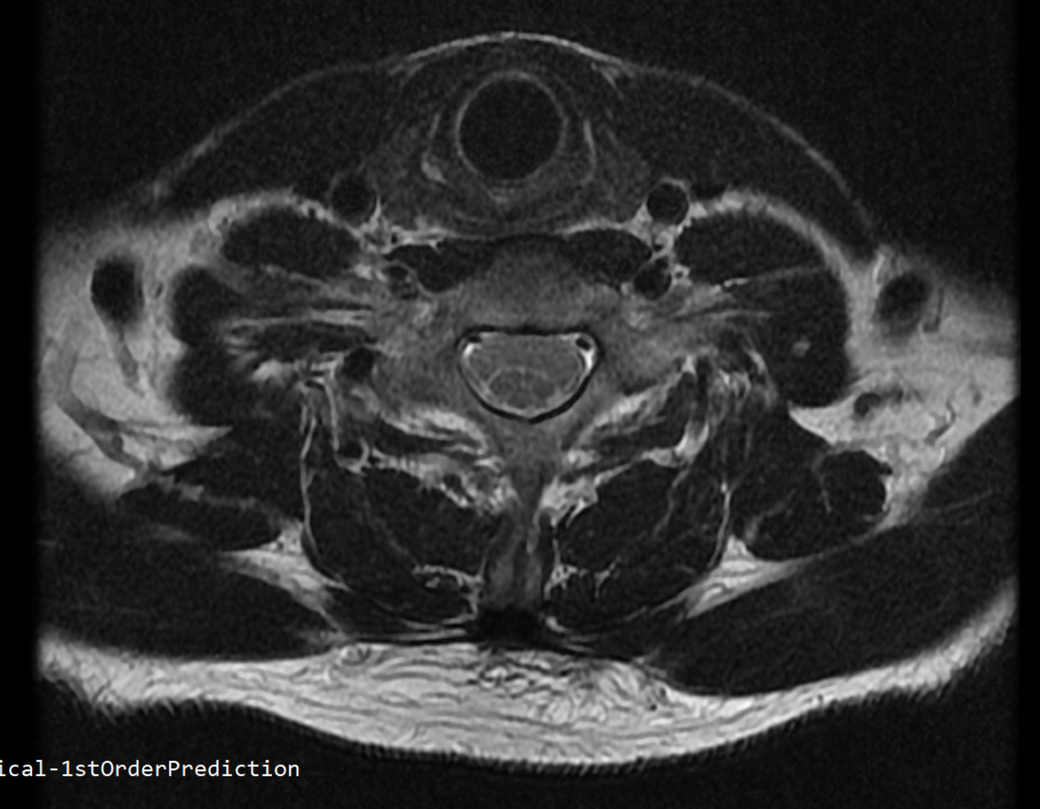

안녕하세요 목 경추 상단부터 순서대로 mri 촬영인데요

전체적으로 봐주시면 감사하겠습니다

• 2번 째 사진